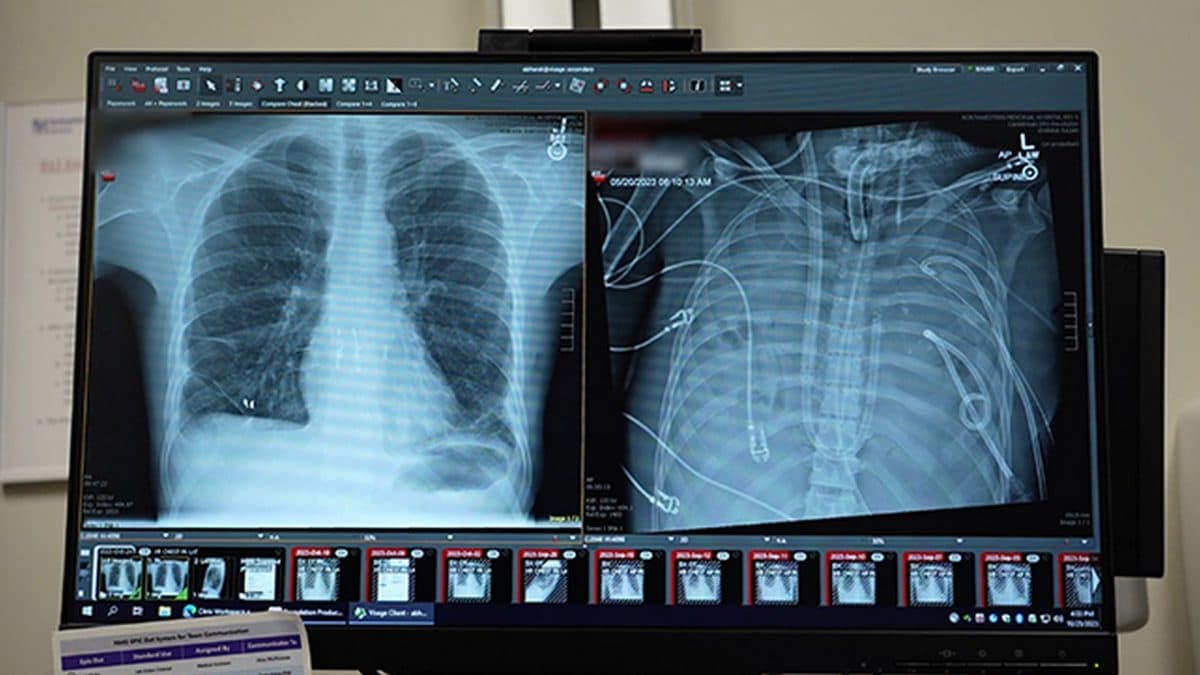

Il merito di questo intervento straordinario è di un equipe di medici della Divisione di Chirurgia Toracica presso la Scuola di Medicina “Feinberg” dell'Università Northwestern di Chicago, che hanno collaborato a stretto contatto con i colleghi dei dipartimenti di Anestesiologia e Patologia e della Divisione di Medicina Polmonare e Terapia Intensiva. Gli specialisti, coordinati dal professor Ankit Bharat, primario di chirurgia toracica e direttore esecutivo del Northwestern Medicine Canning Thoracic Institute, nel 2023 hanno ricevuto il paziente al Northwestern Memorial Hospital sottoposto ossigenazione extracorporea a membrana (ECMO) a causa dell'ARDS innescata dall'influenza.

Terribili le analisi condotte sui polmoni del giovane, devastati dall'infezione. I medici hanno rilevato danni irreversibili, assenza di cellule riparatrici, tessuto completamente sostituito da cicatrici e struttura polmonare liquefatta, una condizione che non avrebbe lasciato scampo al paziente, senza la TAL. I dettagli del case report “Bridge to transplant using a flow-adaptive extracorporeal total artificial lung system following bilateral pneumonectomy” sono stati pubblicati su Med di Cell Press.